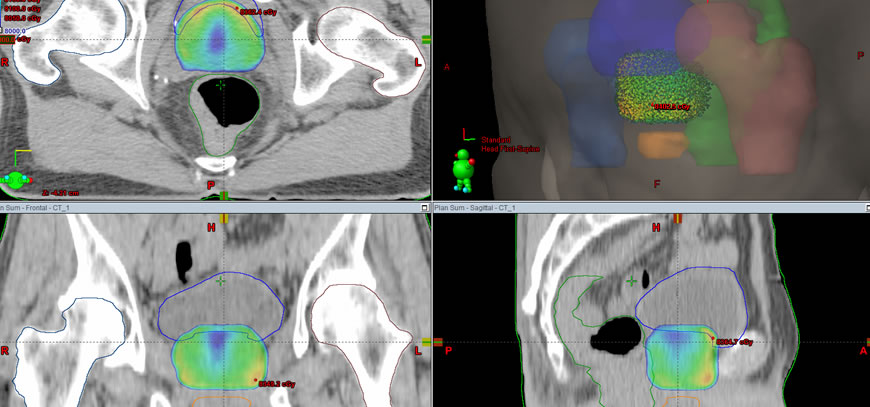

Radioterapia 3D (R-3D)

R-3D es la evolución de la irradiación bidimensional (R-2D) que utilizábamos cuando sólo contábamos con imágenes de radiología simple para planificar los tratamientos (RX convencional).R-3D permite identificar cada órgano y no irradiar áreas o grandes volúmenes como hacías antiguamente cuando no podíamos distinguir entre el tumor y los tejidos vecinos.

Se realiza una tomografía o una resonancia con el paciente en posición de tratamiento. Las imágenes obtenidas son transmitidas por red Dicom al sistema de planificación. - Planificación del tratamiento

Determinación de volúmenes a partir de las imágenes de tomografía o resonancia. Los médicos radioterapeutas definen el tumor y los órganos nobles (sanos). - Definición de campos de tratamiento

El médico radioterapeuta junto con el físico médico diseñan la configuración de haces más adecuada para cada caso. - Optimización de tratamiento

Los médicos radioterapeutas establecen las relaciones dosis- volumen que desean obtener. Se utiliza la planificación directa probando distintas planificaciones para obtener la más conveniente. - Certificación del tratamiento